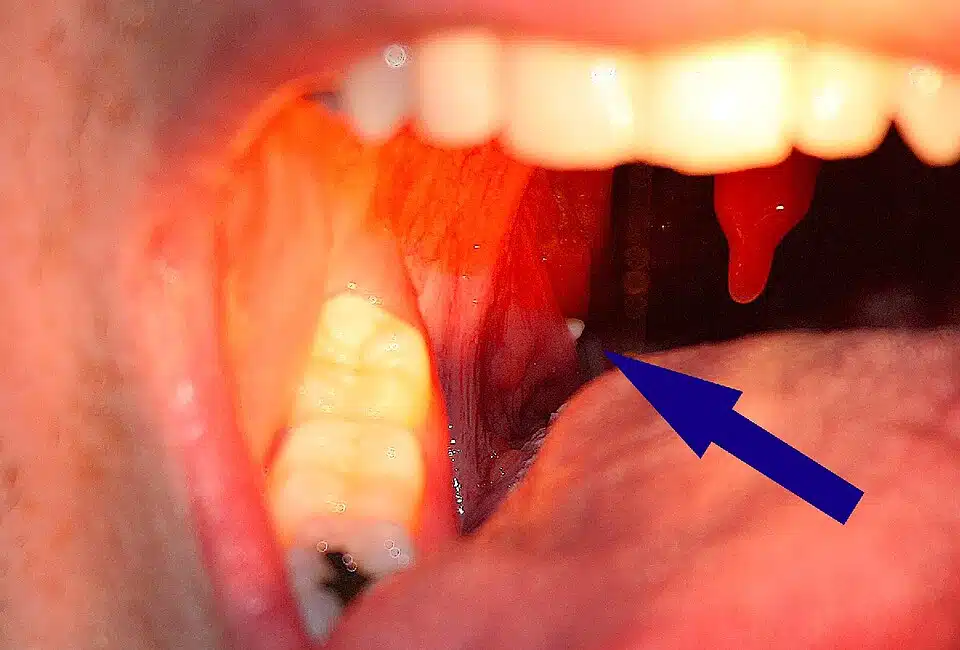

Contrairement aux apparences, ces petites masses ne sont pas des cailloux mais des amalgames de débris organiques. Nos amygdales, avec leurs cavités naturelles (les cryptes), piègent divers éléments : particules alimentaires, cellules desquamées, bactéries. Au fil du temps, ce mélange se solidifie, prenant cette teinte caractéristique entre le blanc cassé et le jaune pâle.

Rassurez-vous, ce processus est généralement sans danger. Cependant, il peut occasionner une sensation désagréable de gêne pharyngée, voire influencer l’haleine de manière significative.